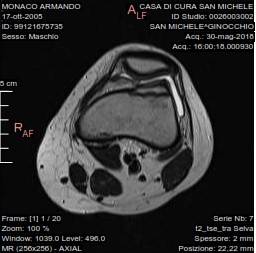

L'esame rm del ginocchio eseguito con apparecchio ad alto campo magnetico con acquisizioni multiplanari ha mostrato:

non evidenti alterazioni di segnale della spongiosa ossea a carattere focale o diffuso, conservata continuità e segnale delle corticali. Ampia incisura osteocondrale della superficie articolare esterna della troclea femorale estesa trasversalmente per 14mm e longitudinalmente per 12mm. Piccolo frammento osteocondrale in camera articolare anteriore sovrarotulea. Conservata morfologia e segnale del menisco laterale e del mediale senza apprezzabili lesioni a loro carico. Regolare continuità e segnale dei legamenti crociati, non evidenti segni di lesioni traumatiche in atto delle altre formazioni capsulo-legamentose esaminate, falda fluida intrarticolare, rotula in asse.